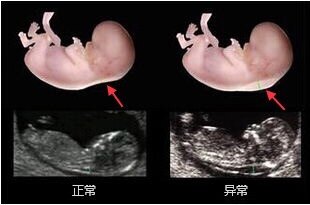

在門診經(jīng)常遇到前來檢查的孕媽問:醫(yī)生,是不是NT值越小越好啊?在回答這個問題之前我們先來了解一下什么是NT?它是怎么形成的,應該在什么時候測以及測量的價值。 NT(NuchalTranslucency)也就是頸部透明層厚度,是指胎兒頸部皮下位于皮膚與深部軟組織之間的無回聲帶。這是一個所有胎兒均會出現(xiàn)的一種超聲征象。 NT是如何形成的? 正常胎兒淋巴回流系統(tǒng)建立之前,少量淋巴液聚集在頸部淋巴管內(nèi),形成NT。14周后胎兒淋巴系統(tǒng)發(fā)育完善,聚集的淋巴液迅速引流到頸靜脈,頸部透明層通常會消退。當淋巴往頸靜脈回流障礙時,過多的淋巴液集聚在頸項部,使皮膚與其下方結(jié)締組織之間半透明組織增厚,有時淋巴管擴張形成頸水腫或頸部水囊瘤。 NT檢查的時間及正常值是什么? NT檢查時間是孕11—13+6周,胎兒頭臀長45-84mm,正常NT值